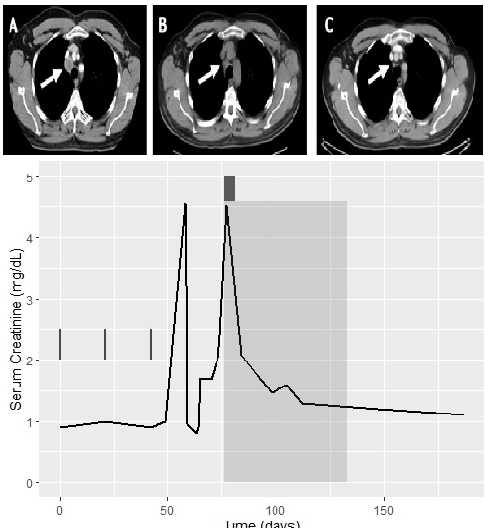

A Case Report of Acute Myeloid Leukemia in a Patient Treated with Pembrolizumab

Case Report

Clin Oncol Case Rep 2021, 4:1 (154)

Case Report

Clin Oncol Case Rep 2021, 4:1 (155)